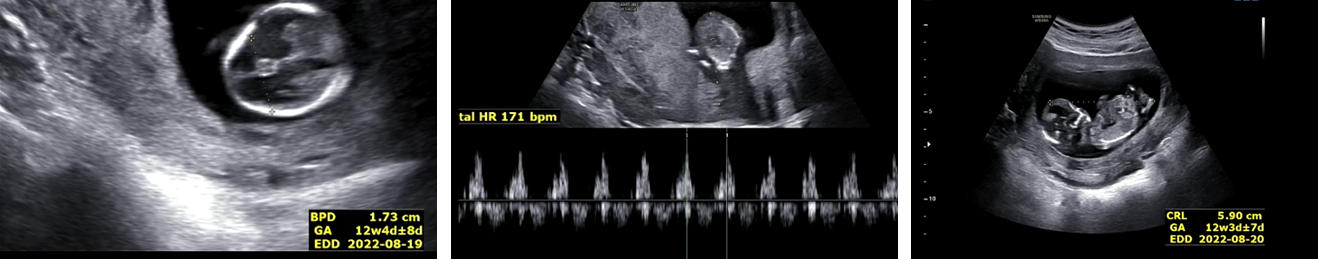

머리 크기 : 1.73 cm , 심장박동수 171 bpm, 크기 5.9cm 초음파 진찰을 봐주셨던 간호사 선생님이 또래에 맞게 건강하게 잘 자라고 있다고 하였다. 엄마 뱃속에서 잘 지내고 있다고 하니 짠하기도 하고 감격스럽기도 하였다. 호띵이 태어나면 같이 맛있는 것도 많이 먹고 여행도 자주 다니고 싶다.